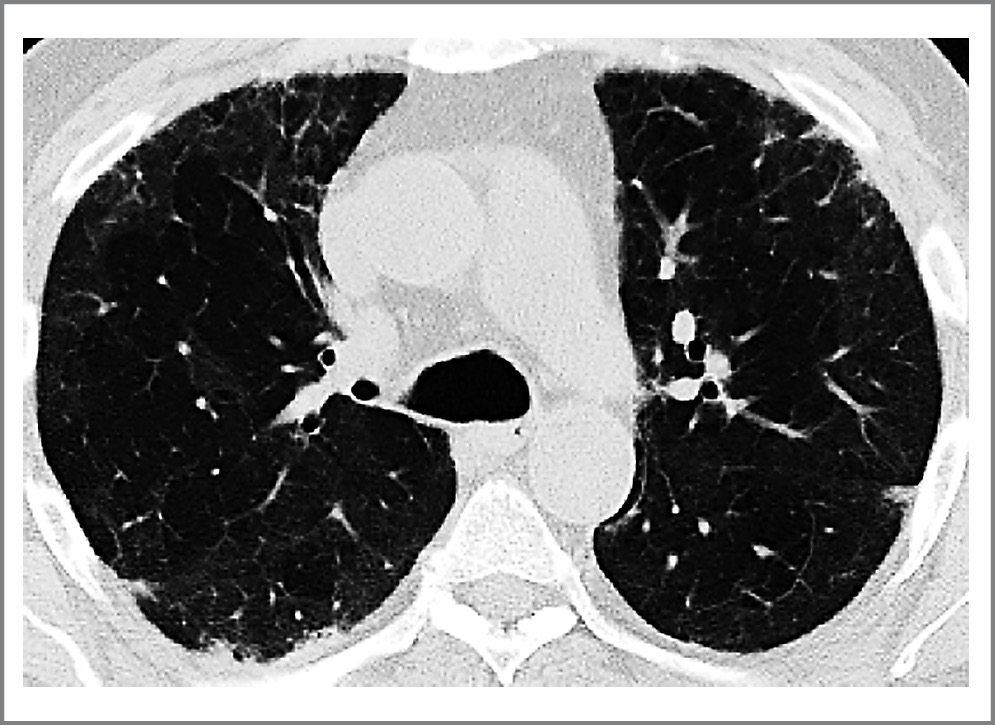

Пациенту установлен диагноз интерстициального заболевания легких (ИЗЛ) – пост-COVID-19-ОП. Начата терапия преднизолоном (20 мг/сут) и ривароксабаном (20 мг/сут). В результате проводимого лечения отмечалась положительная динамика: лабораторно – снижение острофазовых показателей – СРБ до 4 мг/л (0–5); также пациент отмечал уменьшение выраженности одышки. При проведении контрольной КТ в июле 2021 г. отмечался значительный регресс интерстициальных изменений в легких, маркеры воспаления – стабильно в пределах референсных значений. Доза преднизолона медленно снижена до полной отмены в августе 2021 г. без последующего рецидива ОП. В октябре 2021 г. выполнена КТ органов грудной клетки, отмечается выраженная положительная динамика, уменьшение зон «матового стекла» (рис. 3).

Рис. 3. КТ грудной клетки пациента от 10.10.2021. / Fig. 3. Computer tomography scan of the patient's chest from 10/10/2021.